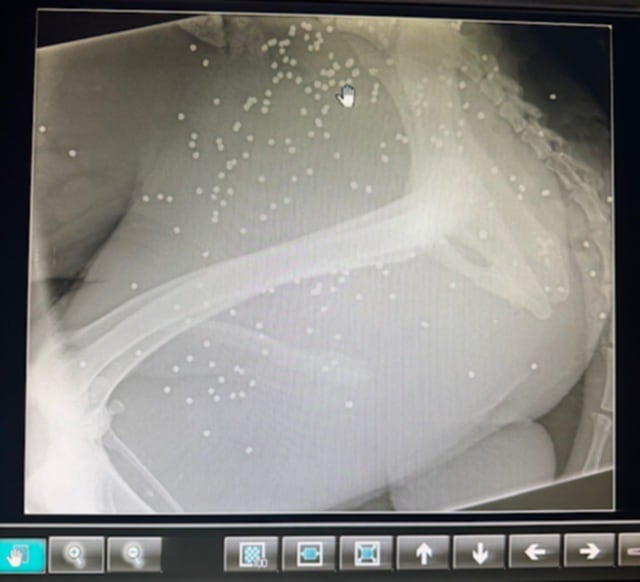

Στις 3 Οκτωβρίου φιλόζωοι εντόπισαν ένα από τα ελάχιστα σκυλιά που έχουν επιζήσει στο Κρυονέρι Αιτωλοακαρνανίας πυροβολημένο. Η αρχική εντύπωση του κτηνιάτρου ήταν ότι το σκυλί έχει δαγκωθεί από άλλο ζώο εντούτοις η ακτινογραφία έδειξε τι έχει συμβεί. Το σώμα του είναι γεμάτο σκάγια…

Ο Περσέας βρέθηκε πυροβολημένος, με το σώμα του γεμάτο σκάγια. Ευτυχώς τραυματισμενος γύρισε στο μέρος που τον φρόντιζαν να ζητήσει βοήθεια.. Σοβαρό τραύμα, δεν  μπορεί ακόμη να σταθεί όρθιος.

Πρέπει να κάνει πλαστική στο σημείο που πυροβολήθηκε, γιατί είναι εκτεθειμένο το οστό του.